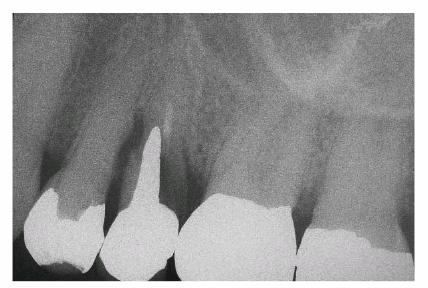

restoration of endodontically treated teeth (Figur 323s1823d es 18-20A 18-20B, and 18-20C). If an adequate ferrule is

Figur 323s1823d e 18-19: Ferrule design resists wedging force of post.

Figur 323s1823d e 18-20A: Proper ferrule design on preparation for porcelain-fused-to-metal crown.

Figur 323s1823d e 18-20B: Radiograph showing cast post and core after cementation. Note that the post is more than one-third of the diameter of the root at the cement-enamel junction and is tapered. Tooth preparation did not exhibit ferrule design.

Figur 323s1823d e 18-20C: Same clinical case as in Figur 323s1823d e 18-20B after 8 years. Note the oblique root fracture. Such a fracture could be prevented by a more conservative post in combination with proper ferrule design in the crown preparation.